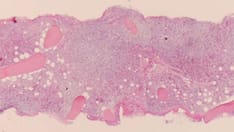

Bone marrow consists of stem cells, which are large, "primitive," undifferentiated cells supported by fibrous tissue called stroma. There are two main types of stem cells, and thus, bone marrow consists of two types of cellular tissue. One type of stem cell is involved in producing blood cells, and the other is involved in producing stromal cells, which are responsible for the supporting stroma. For more information about the relevant anatomy, see Bone Marrow Anatomy.

Sampling of the marrow consists of aspiration of the cellular component, acquisition of tissue fragments, or both. Aspiration of the marrow has been primarily utilized for cytologic assessment, with analysis directed toward assessing the morphology and obtaining a differential cell count. Further sampling allows material to be directed toward other ancillary tests, such as cytogenetics, molecular studies, microbiologic cultures, immunohistochemistry, and flow cytometry.

Biopsies, on the other hand, allow evaluation of the marrow’s overall cellularity, detection of focal lesions, and determination of the extent of infiltration by various pathologic entities. [2, 3, 4]